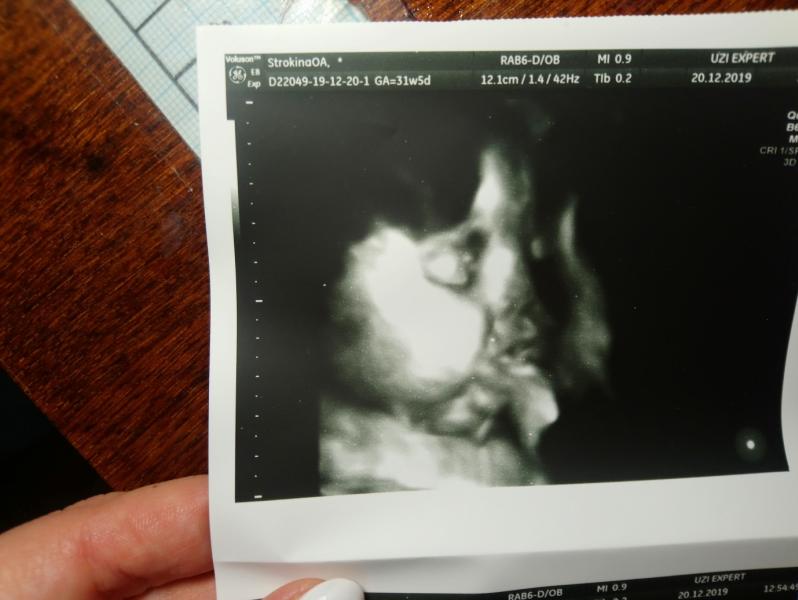

единственная радость это что второй в животике и пока он только мой, и пока он любит только меня❤️ сегодня были на узи, увидела его щёчки